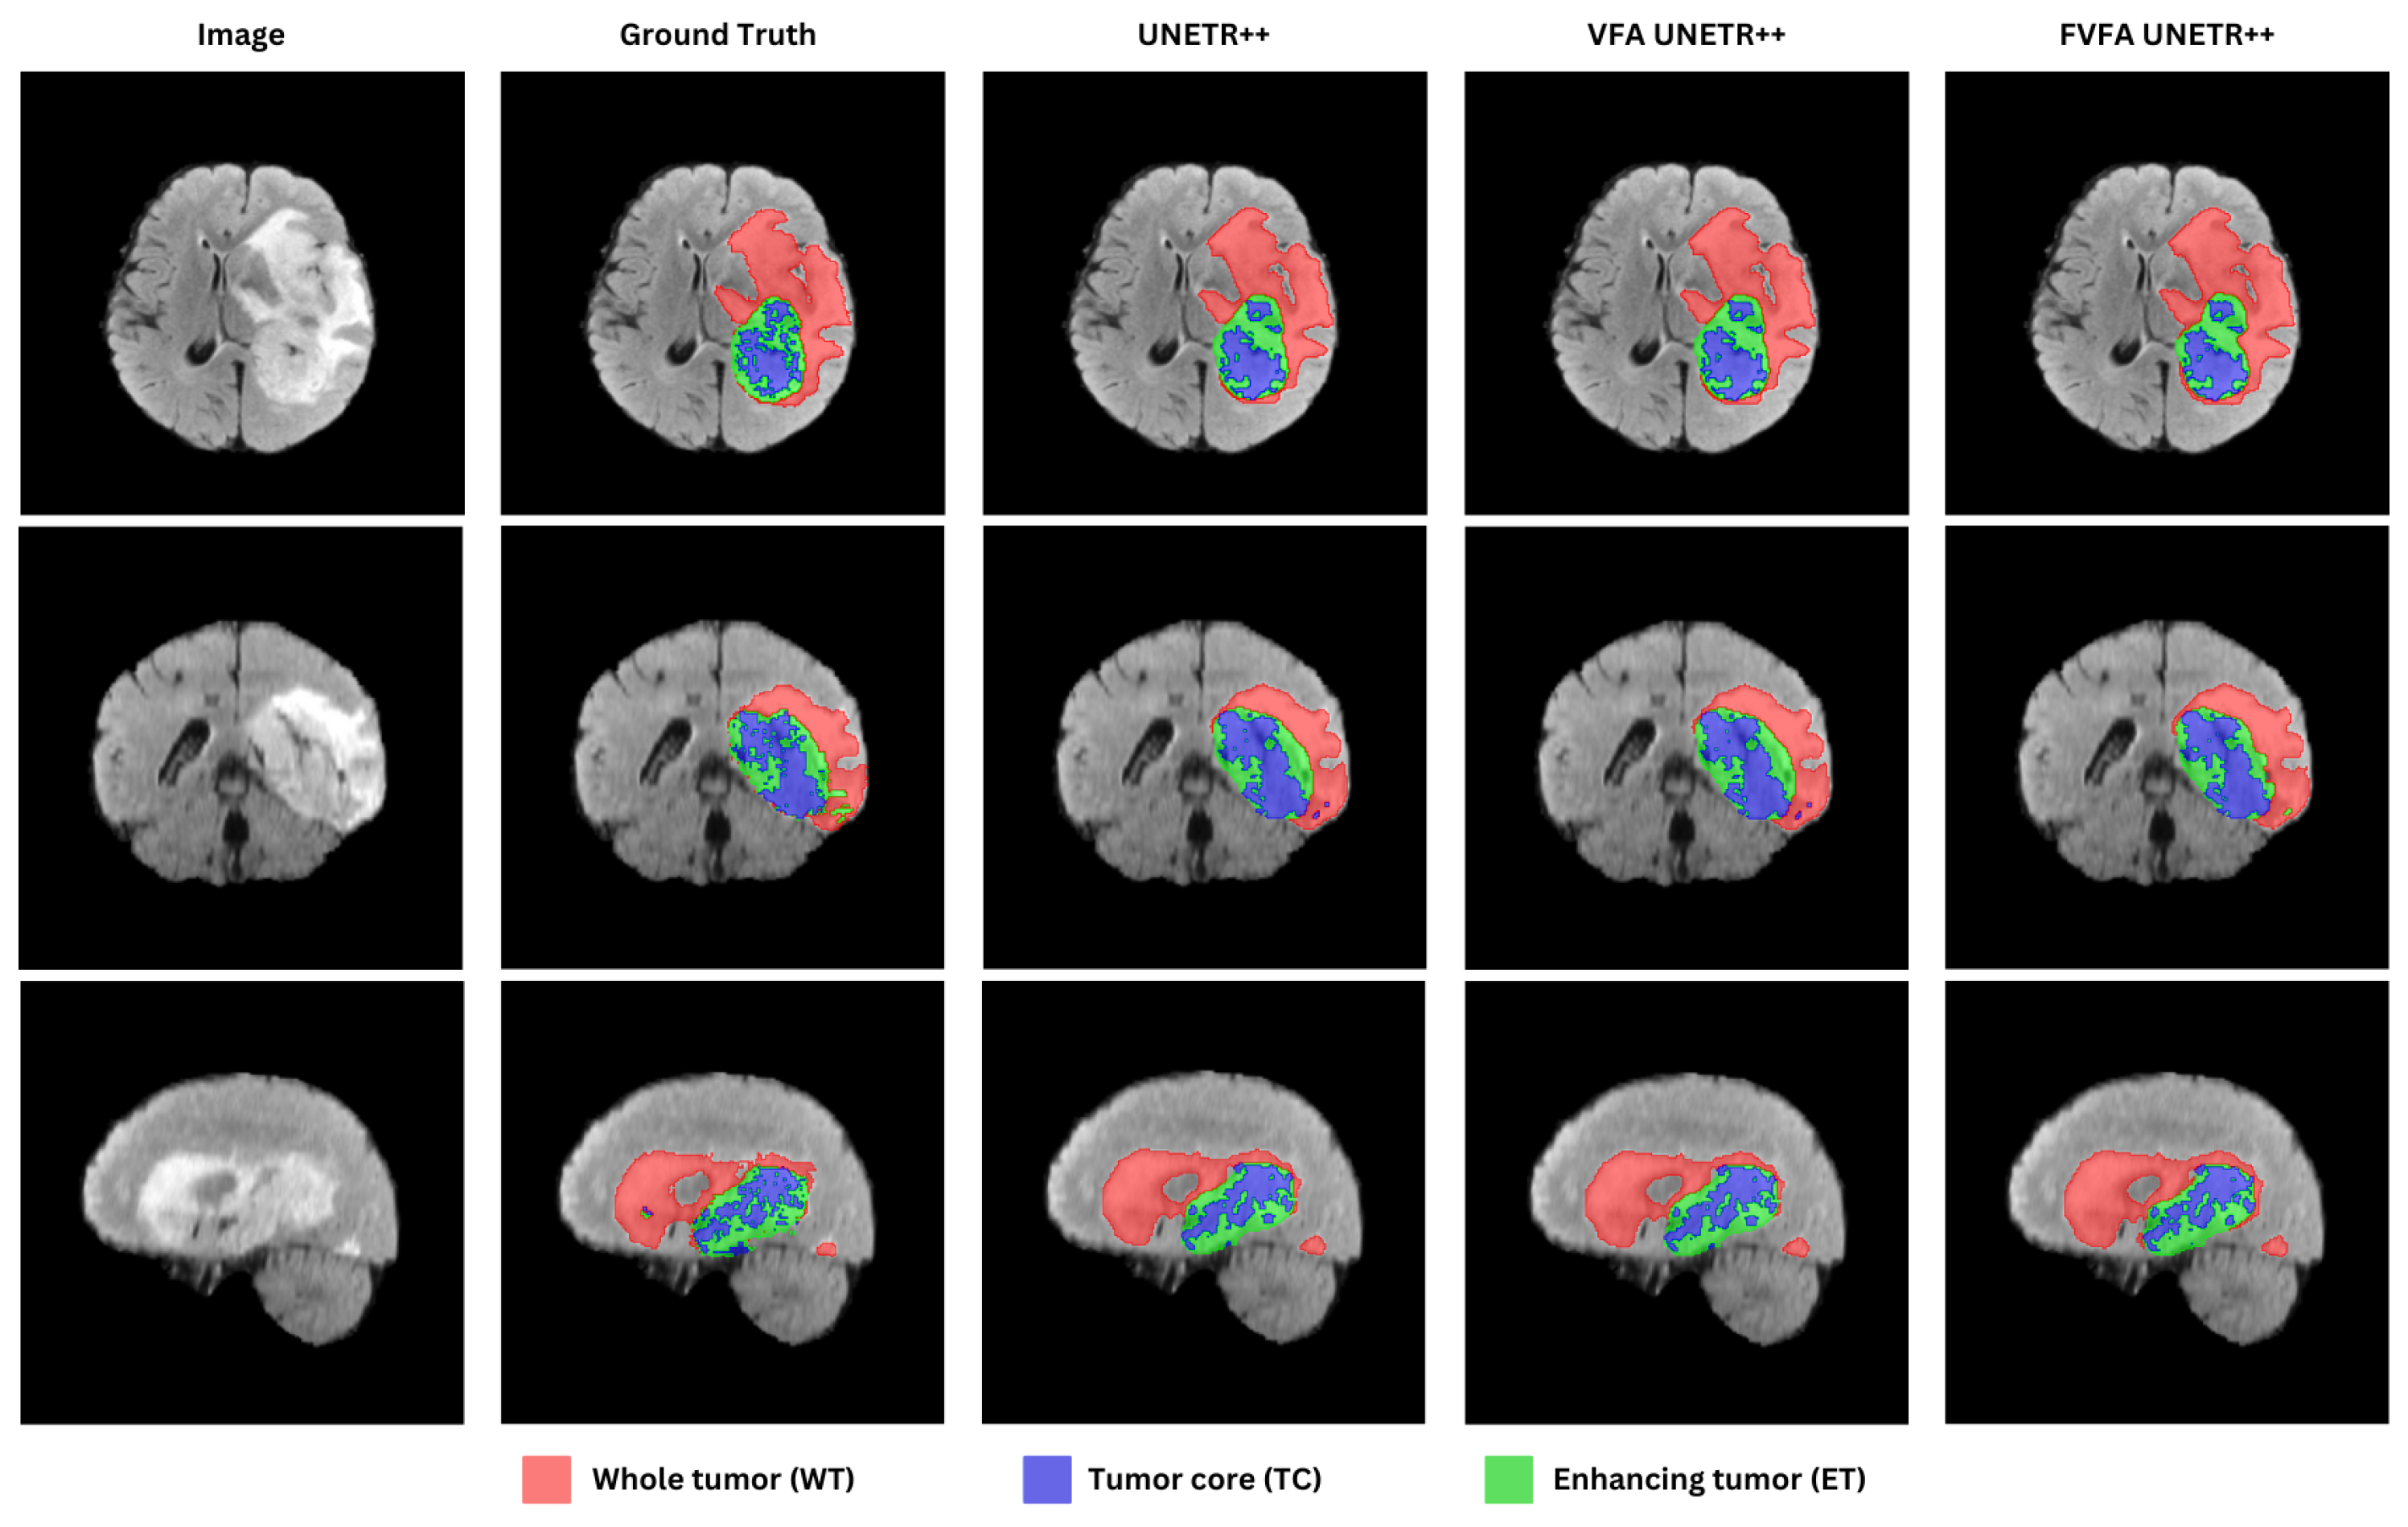

- BraTS: This dataset includes 484 MRI images with four modalities (FLAIR, T1w, T1gd, and T2w). The dataset is annotated for peritumoral oedema, GD-enhancing tumour, and necrotic/non-enhancing tumour core.

4.2.3. BraTs Dataset

| Methods | Params | FLOPs | Mem | DSC (%) |

|---|---|---|---|---|

| UNETR [31] | 92.5 | 153.5 | 3.3 | 81.2 |

| SwinUNETR [36] | 62.8 | 572.4 | 19.7 | 81.5 |

| nnFormer [32] | 149.6 | 421.5 | 12.6 | 82.3 |

| UNETR++ [12] | 42.6 | 70.1 | 2.7 | 82.7 |

| VFA UNETR++ | 28.6 | 72.29 | 3.1 | 82.8 |

| FVFA UNETR++ | 21.4 | 78.3 | 5.8 | 82.4 |

| Methods | Training Time | Inference Time | HD95 |

|---|---|---|---|

| UNETR++ [12] | 244.14 | 5.69 | 5.27 |

| VFA UNETR++ | 245.21 | 5.28 | 5.01 |

| FVFA UNETR++ | 248.58 | 7.94 | 5.08 |